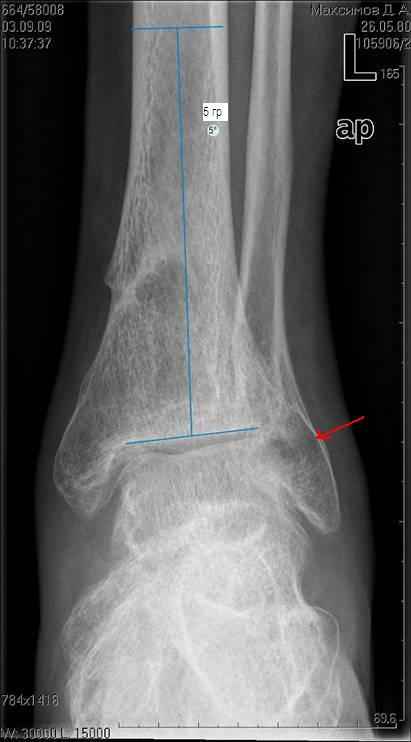

Травму он получил на работе, левая голень со стопой оказались зажатыми между двумя тяжелыми предметами. В результате открытые переломы 1,2,3 плюсневых костей с размозжением мягких тканей над ними, открытый перелом наружной лодыжки со смещением дистального отломка кзади и подвывихом стопы кнаружи с размозжением мягких тканей над лодыжкой, закрытые переломы внутренней лодыжки и дистального метэпифиза большеберцовой кости.

Учитывая наличие размозжения тканей стопы и области голеностопного сустава лечили в аппарате внешней фиксации. Переломы срослись, однако имеет место незначительный подвывих стопы кнаруже и неправильно сросшийся отломок наржной лодыжки (смещен кзади)

Клинически левый голеностопный сустав не отечный,пальпация всех структур данного сустава безболезненна. Имеет место ограничение тыльного сгибания стопы (сгибание к тылу стопы составляет до 10-15 гр), в связи с этим имеет место гиперподвижность в суставе Шопара.